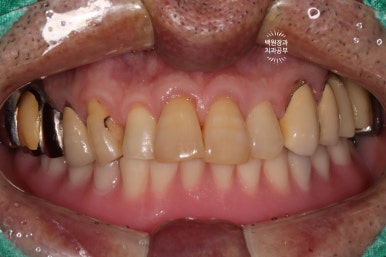

저희 치과에 내원하셨을 당시 입안 사진입니다.

사실 사진만으로는 그 불편함을 느끼기가 어려우실텐데요, 아래는 비교적 최근에 제작된 깔끔한 전체틀니를 사용하고 계셨고, 위 어금니는 만성치주염에 이환되긴 했지만 형태를 모두 갖추고 있었습니다.

아래턱에 사용하고 계신 전체틀니에 매우 불만족하고계신 상태였습니다.

아래턱에는 혀가 있기 때문에, 전체틀니를 사용하면 말하거나 밥먹을 때 무조건 바로 떨어져버립니다....

그래서 입안 사진 찍는 것 조차 힘들었어요. 자꾸 떨어졌기 때문에......